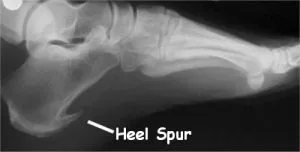

Plantar fasciitis is a common and often painful condition affecting the underside of the foot and is a leading cause of foot pain, particularly in the heel. It is one of the leading causes of heel pain and is sometimes associated with heel spurs. The term plantar fasciitis is used when inflammation is present, while plantar fasciosis refers to a more chronic condition involving tissue degeneration without inflammation.